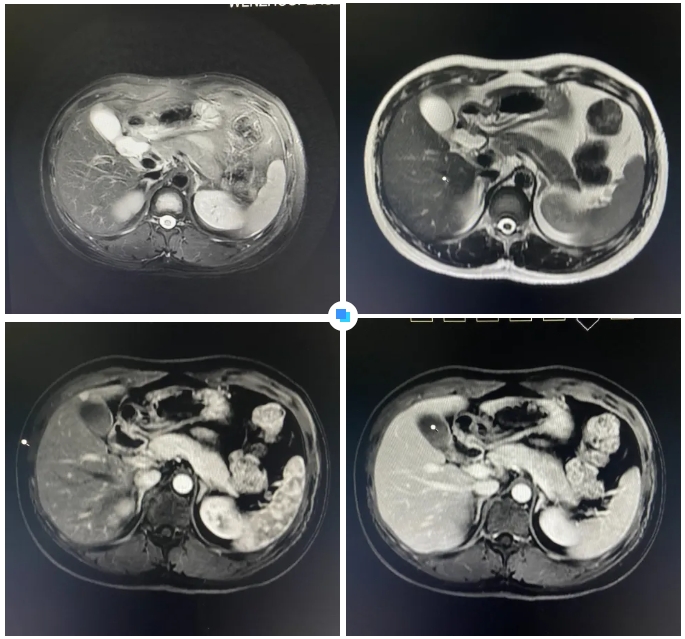

最近,和平國際醫(yī)院影像中心團(tuán)隊如同“神探般”揪出了隱藏在26歲小伙體內(nèi)7mm的微小肝癌。

其實(shí),診斷過程中還有一個小插曲:在和平國際醫(yī)院被初步查出疑似小肝癌病灶后,患者馬上前往上海大三甲醫(yī)院進(jìn)行再次檢查,結(jié)果并沒有發(fā)現(xiàn)病灶。

▲ 和平國際醫(yī)院影像診斷報告

但和平國際醫(yī)院的影像報告引起了三甲醫(yī)院專家的重視。通過將兩家醫(yī)院的影像資料進(jìn)行對比分析,最終找到了患者肝臟內(nèi)的7mm病灶。隨后的手術(shù)證實(shí),該病灶確實(shí)為微小肝癌。

在被問到如何發(fā)現(xiàn)隱藏如此深的病灶時,和平國際醫(yī)院影像中心執(zhí)行主任侯文杰講到,該病灶在平掃T1、T2項都非常不清楚,只有彌散加權(quán)的情況下,病灶區(qū)域顯示出輕微的高信號,這一細(xì)微線索引起了他的高度關(guān)注。

隨后的增強(qiáng)核磁掃描發(fā)現(xiàn),在動脈期病灶顯著強(qiáng)化,而在門脈期明顯減退,這一特征與微小肝癌的表現(xiàn)高度吻合。

“肝癌不可怕,早期發(fā)現(xiàn)是關(guān)鍵。”侯文杰主任講到,肝癌的五年生存率較低,但早期的小肝癌一旦發(fā)現(xiàn),預(yù)后效果會非常好。磁共振(MR)檢查可以發(fā)現(xiàn)亞厘米級肝癌、乃至癌前不典型增生結(jié)節(jié),為臨床醫(yī)生開展腫瘤早期手術(shù)切除術(shù)或介入等相關(guān)外科治療方案提供了精準(zhǔn)的影像依據(jù)。